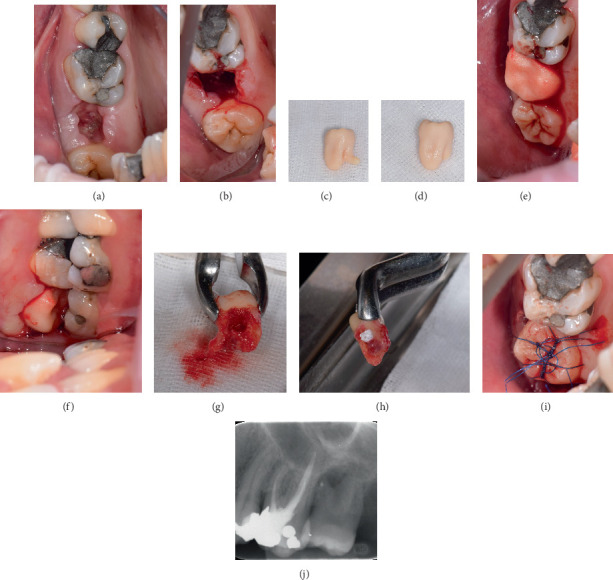

Tooth autotransplantation is a procedure in which a donor tooth is transplanted within the same patient's jaw to replace a missing tooth. Donor tooth root morphology and periodontal ligament integrity are key factors influencing success. We report a semi-immediate autotransplantation of a maxillary third molar with a 90° divergent root into a site previously affected by a periapical abscess. After the extraction of the compromised tooth (#15) and removal of the interradicular septum, the site was left to heal to allow soft tissue closure and infection resolution. During this period, CBCT imaging and a 3D-printed donor tooth replica (CARP model) were used to plan the procedure, including the intended root amputation. Two weeks later, autotransplantation was performed. The recipient site only required soft tissue and granulation tissue management, with no additional bone preparation, allowing for a minimally traumatic approach. The donor tooth was transplanted with an extraoral time of under 6 min. At the 18-month follow-up, the tooth remained functional, asymptomatic, and radiographically stable. This case highlights the feasibility of delayed autotransplantation following infection and the clinical value of combining imaging with prototyping in surgical planning-particularly when dealing with donor teeth with unfavorable root anatomy.